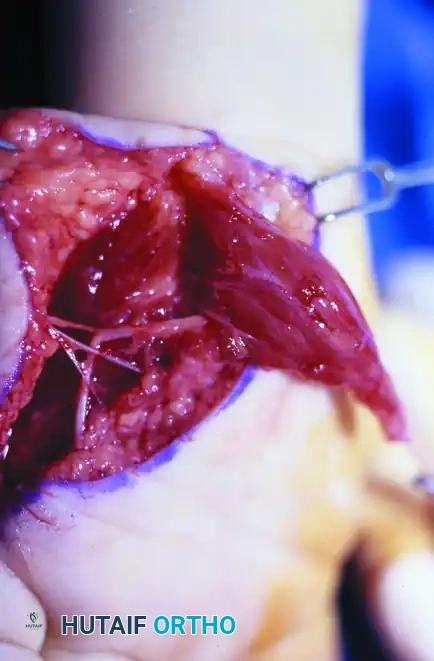

Intraoperative photograph demonstrating the Huber opponensplasty. The abductor digiti minimi muscle belly has been mobilized on its neurovascular pedicle and is being routed subcutaneously across the palm to reconstruct the deficient thenar eminence.